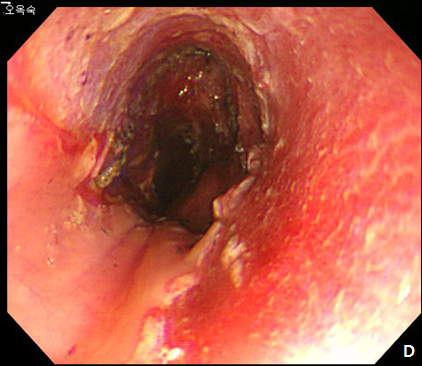

Figure 5 Submucosal tunneling endoscopic resection (STER) of esophageal subepithelial tumor (SET).

(A) Submucosal tunneling was made to approach and expose the tumor. (B) Dissection of the tumor was performed by using an insulated-tip knife. (C) After resection of the tumor, mucosal integrity was preserved as flat. (D) Entry site was sealed by using endoscopic clips.